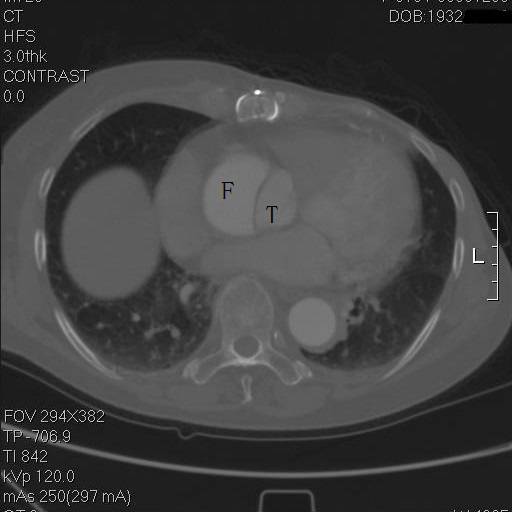

患者是一例A型主动脉夹层,上图中F示假腔,T示真腔,这没什么奇怪。但仔细一看,胸骨的边缘具有高密度影,中间还有一小片低密度区,这例病例接受过前胸正中开胸的手术。

是的,回顾其病史,她一年半前,罹患A型主动脉夹层,第一内膜破裂口在右冠上方,夹层延续到弓部,在弓上分支开口处撕裂形成了出口,她接受了一种显得有些奇怪的术式。

往上阅片,假腔内竟然有一个支架影!